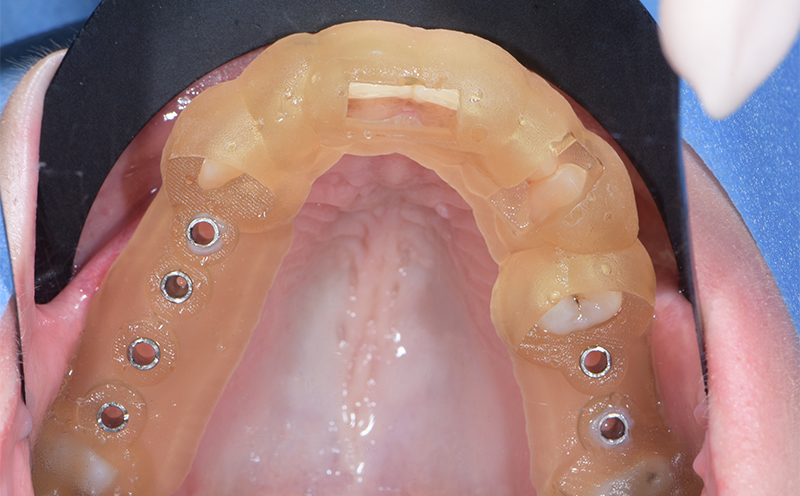

Fig. 24 : guide chirurgical en bouche avant la chirurgie.